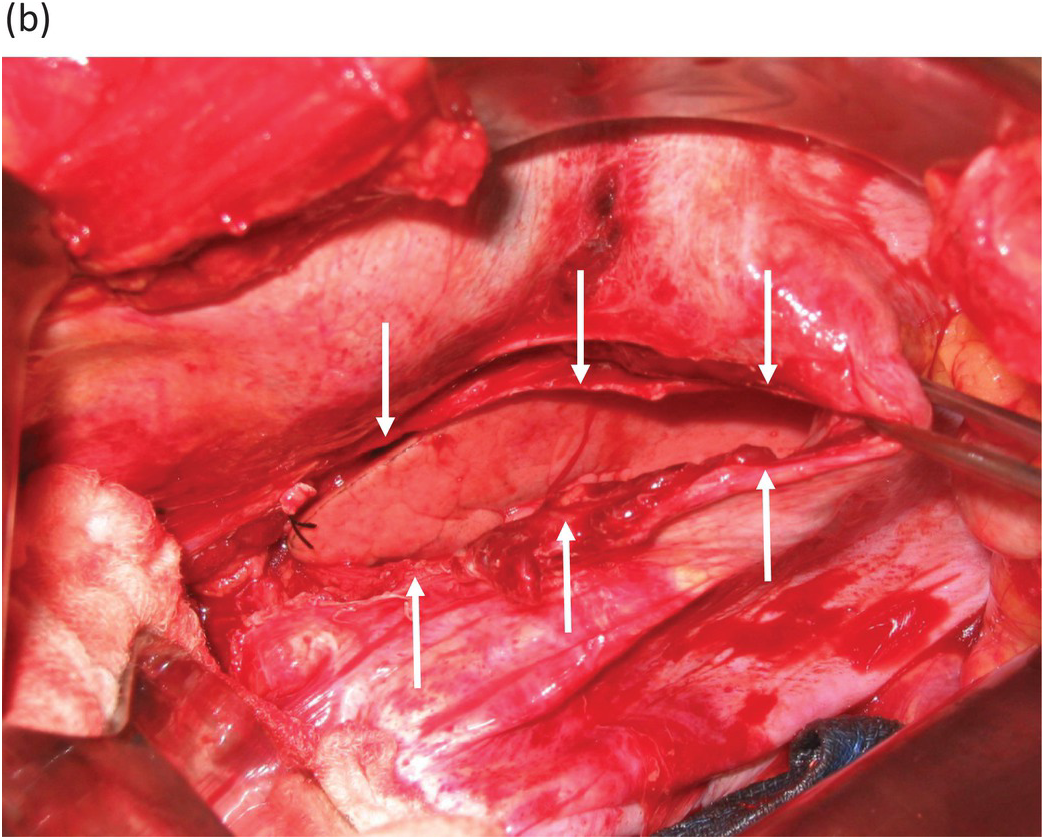

Atlas of Surgical Techniques in Trauma